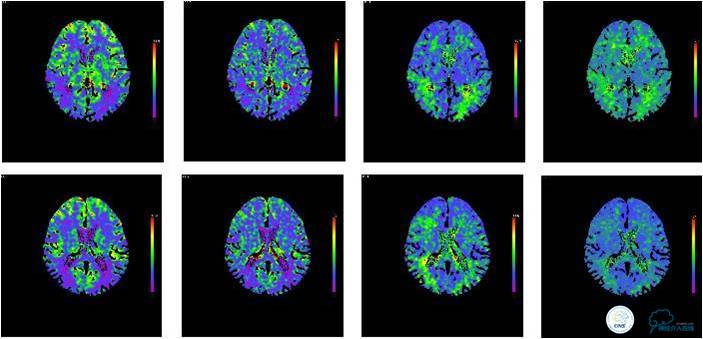

患者入院后,完善颅内CTA(图1)及血管造影(图2~3)检查,发现右侧颈内动脉颅内段闭塞,右侧大脑前动脉依靠左侧颈内动脉系统通过前交通动脉供血,右侧大脑中动脉供血区则依赖于右侧大脑前动脉(ACA)软脑膜代偿供血,左侧大脑中动脉闭塞,依靠一少见血管代偿供血,该血管起自左侧大脑前动脉A2段起始部,代偿供应左侧大脑中动脉供血区。由于该患者灌注CT(图4)未见明显低灌注区,遂给予患者抗血小板、降脂及控制危险因素治疗出院。出院后电话随访未再出现过上述症状。

图4:患者入院后灌注CT提示未见明显低灌注区域。